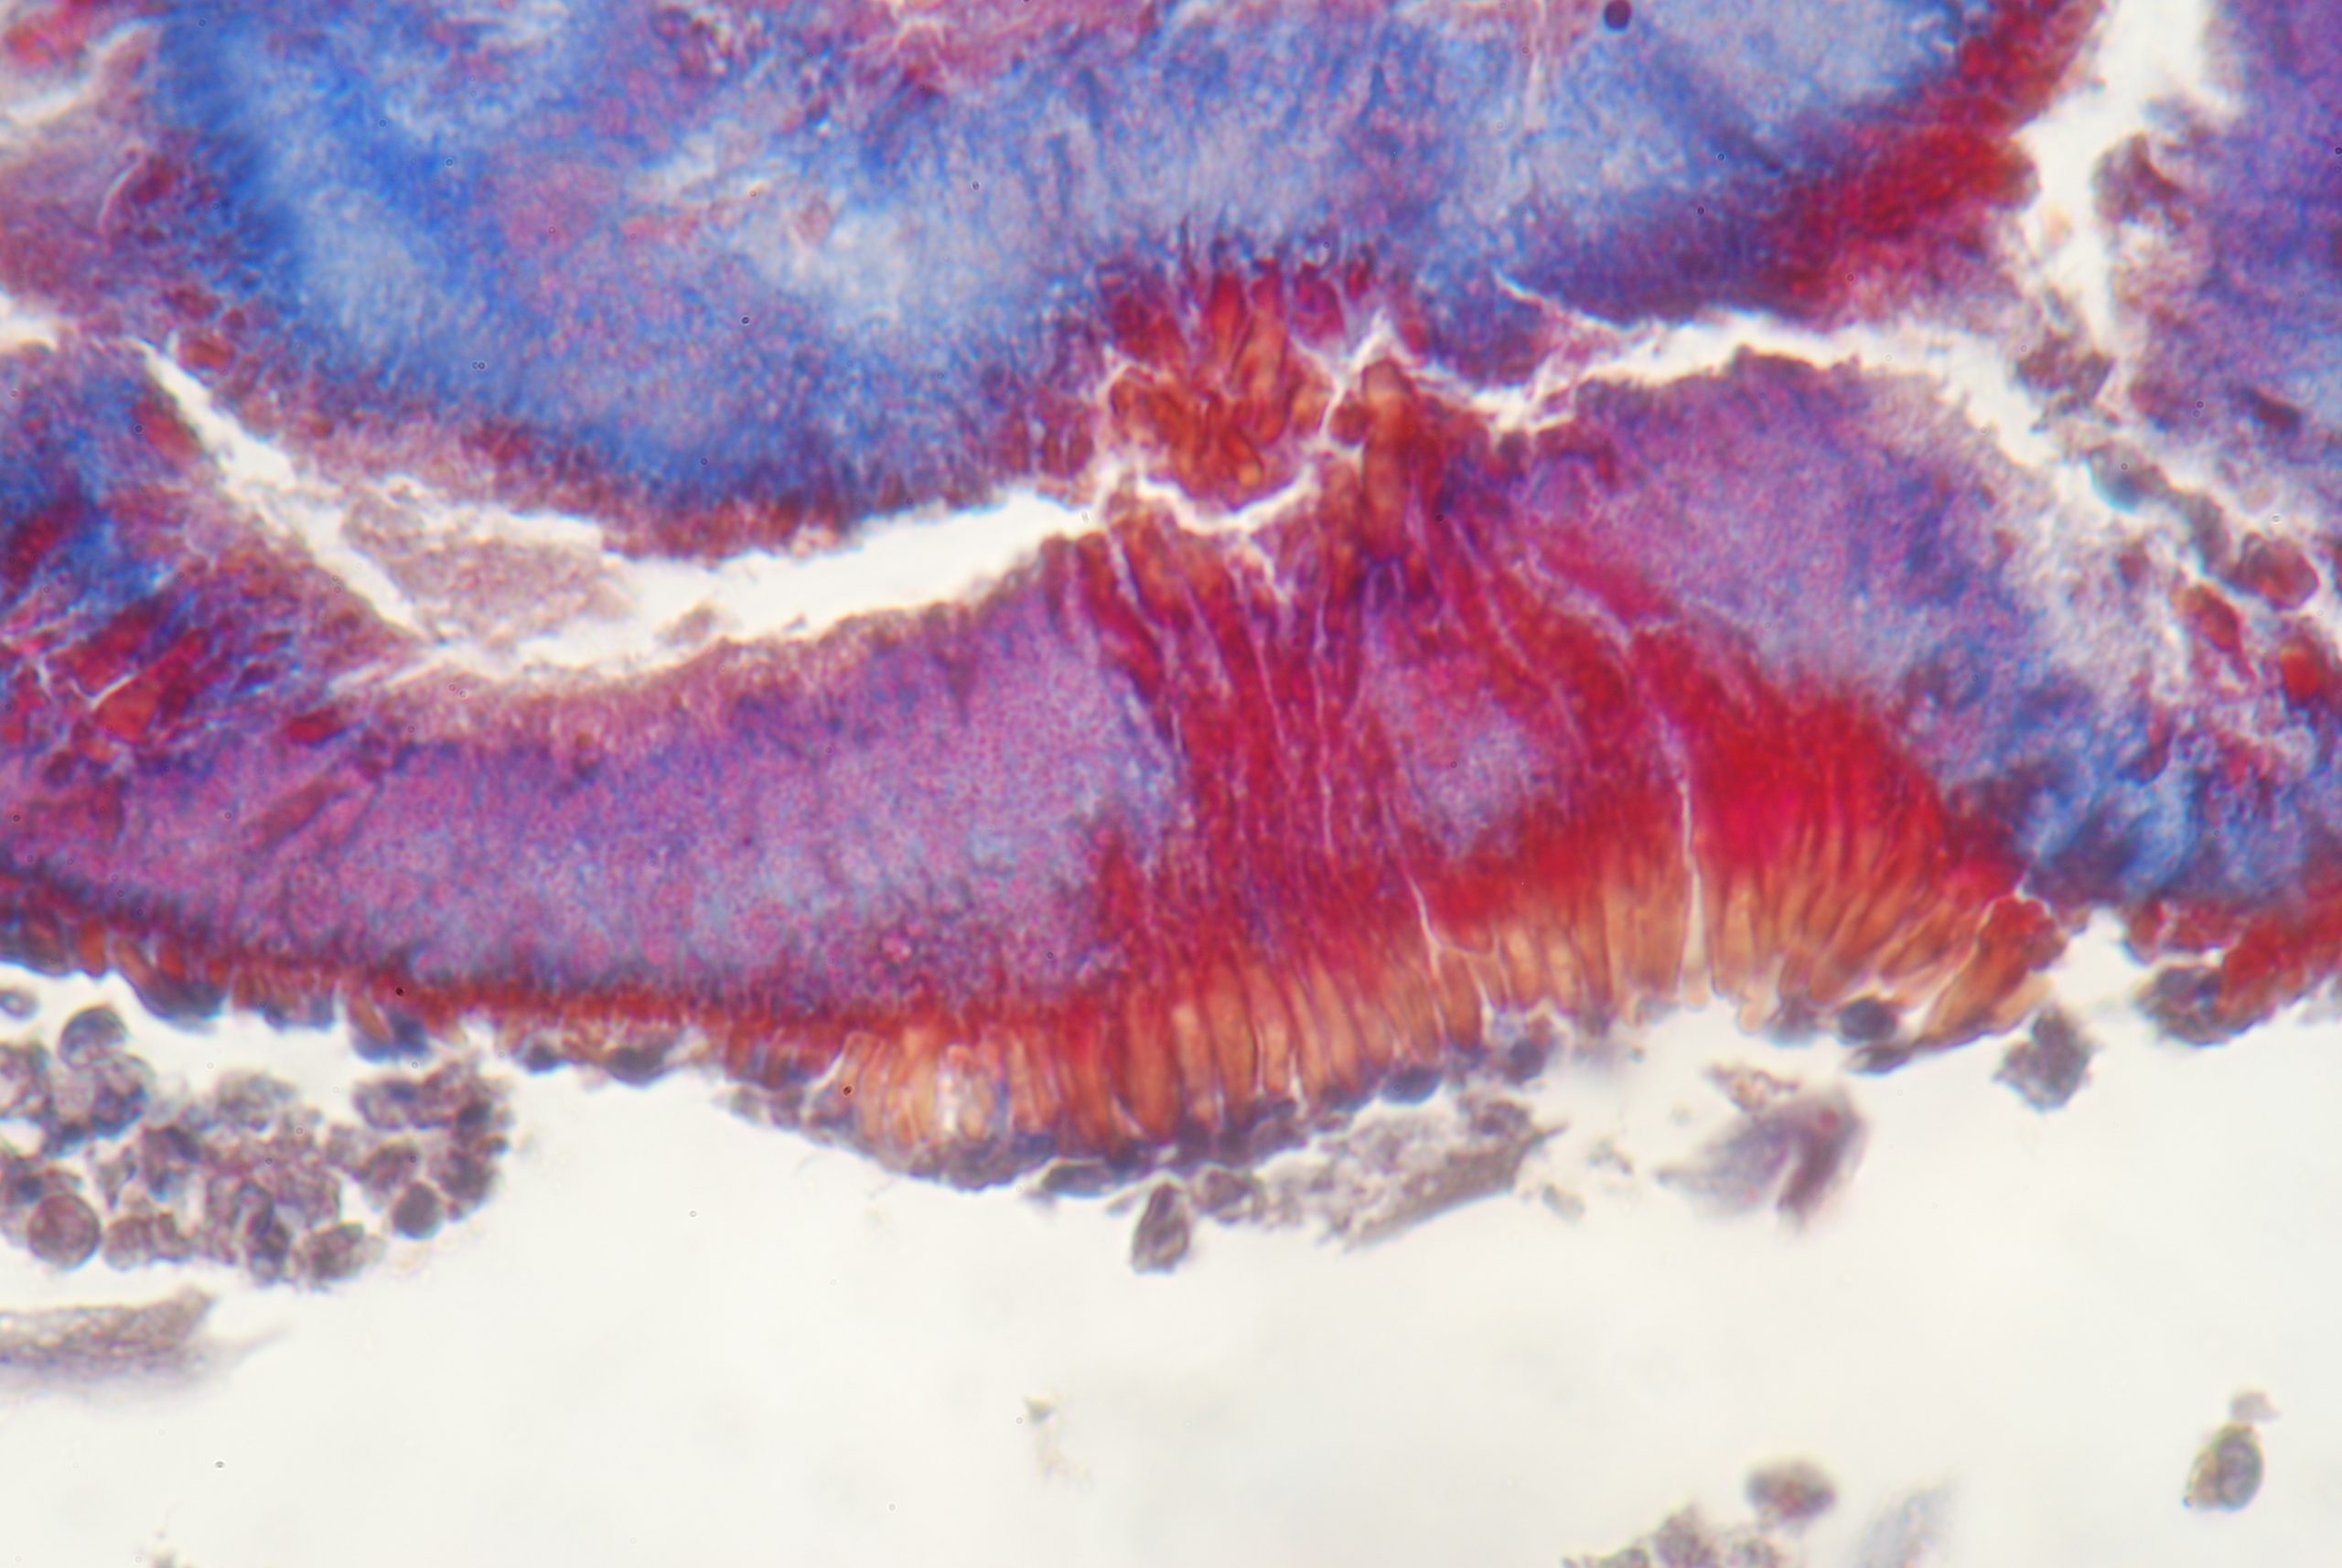

Στο δεύτερο μέρος με τίτλο «Διάγνωση παθήσεων του πολφού και των περιακρορριζικών ιστών» πραγματοποιείται αναλυτική περιγραφή των διαγνωστικών κατηγοριώντων πολφικών και περιακρορριζικώνπαθήσεων. Σε μια προσπάθεια ερμηνείας των παθολογικών καταστάσεων που περιγράφονται, στα πρώτα κεφάλαια του δεύτερου μέρους αναλύονται οι μηχανισμοί παθοφυσιολογίας του συστήματος οδοντίνης πολφού, η κατανόηση των οποίων αποτελεί βασική προϋπόθεση αντίληψης των διαγνωστικών κατηγοριών και παθήσεων.